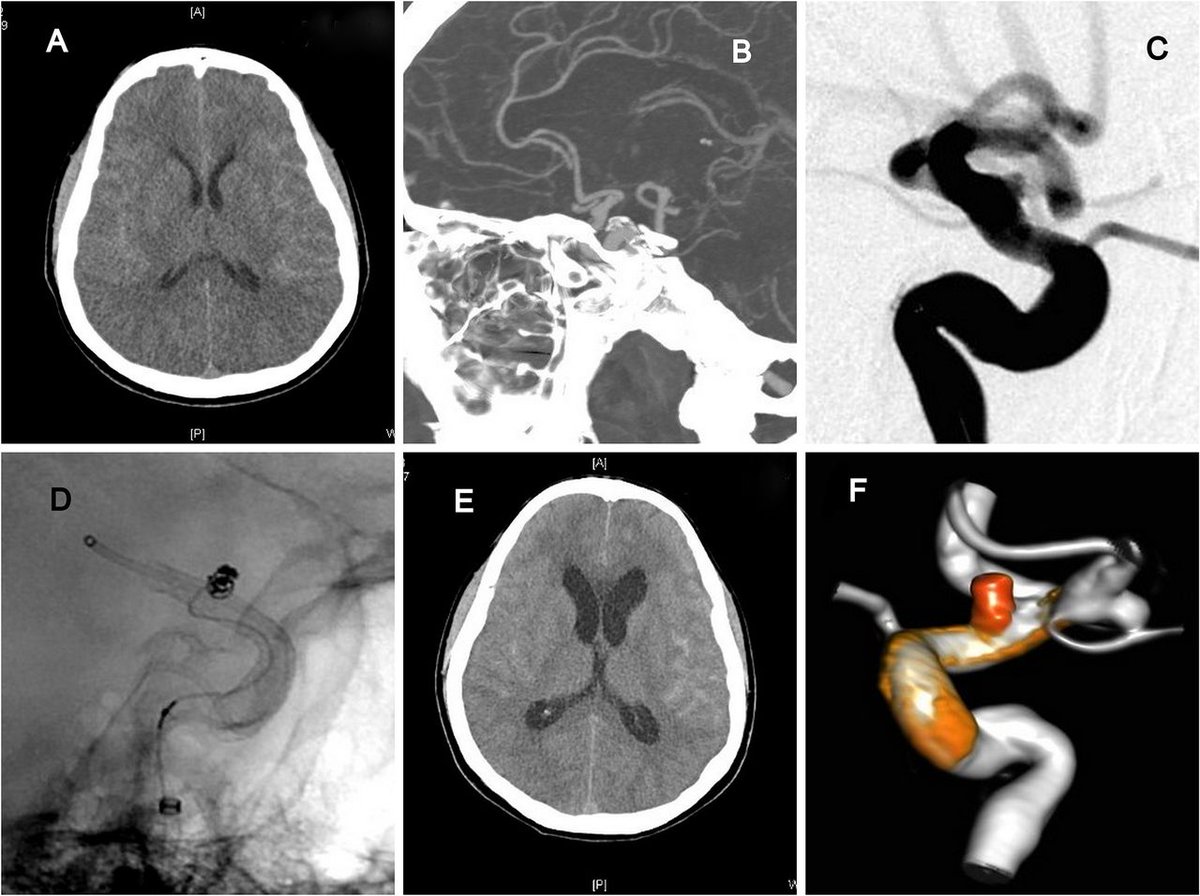

Honored to have our article on using sagittal CTA to identify the Sylvian triangle for M2,M3,M4 occlusions published (helps ID candidates for distal occlusion tx). Article dedicated to our NeuroIR mentor Dr. Irwin Keller who passed away last year. #neuroir #stroke #neuroradiology